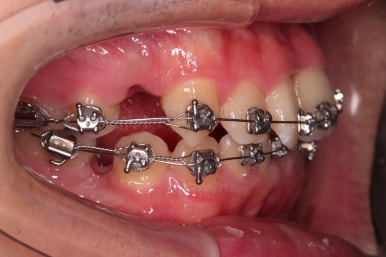

초진 시, 입안의 모습입니다.

치아를 모두 담기에 골격이 매우 작았어요.

이런 경우 치열이 ㅃ뚤어지거나 입이 튀어나오거나 뻐드렁니가 되거나 특정 치아가 묻혀버리거나 맨 뒤치아가 마치 사랑니처럼 올라오지 못한다거나 등등의 문제가 생기는데요.

이번 환자분은 전반적으로 삐뚠 상황이었어요.

앞니도 대칭적으로 삐뚤어져 흔히 나비치아라고 하는 형태로 보이고, 아랫니들은 U자 아치의 형태가 찌그러져 있네요.

당연히 교합도 맞지 않고요.